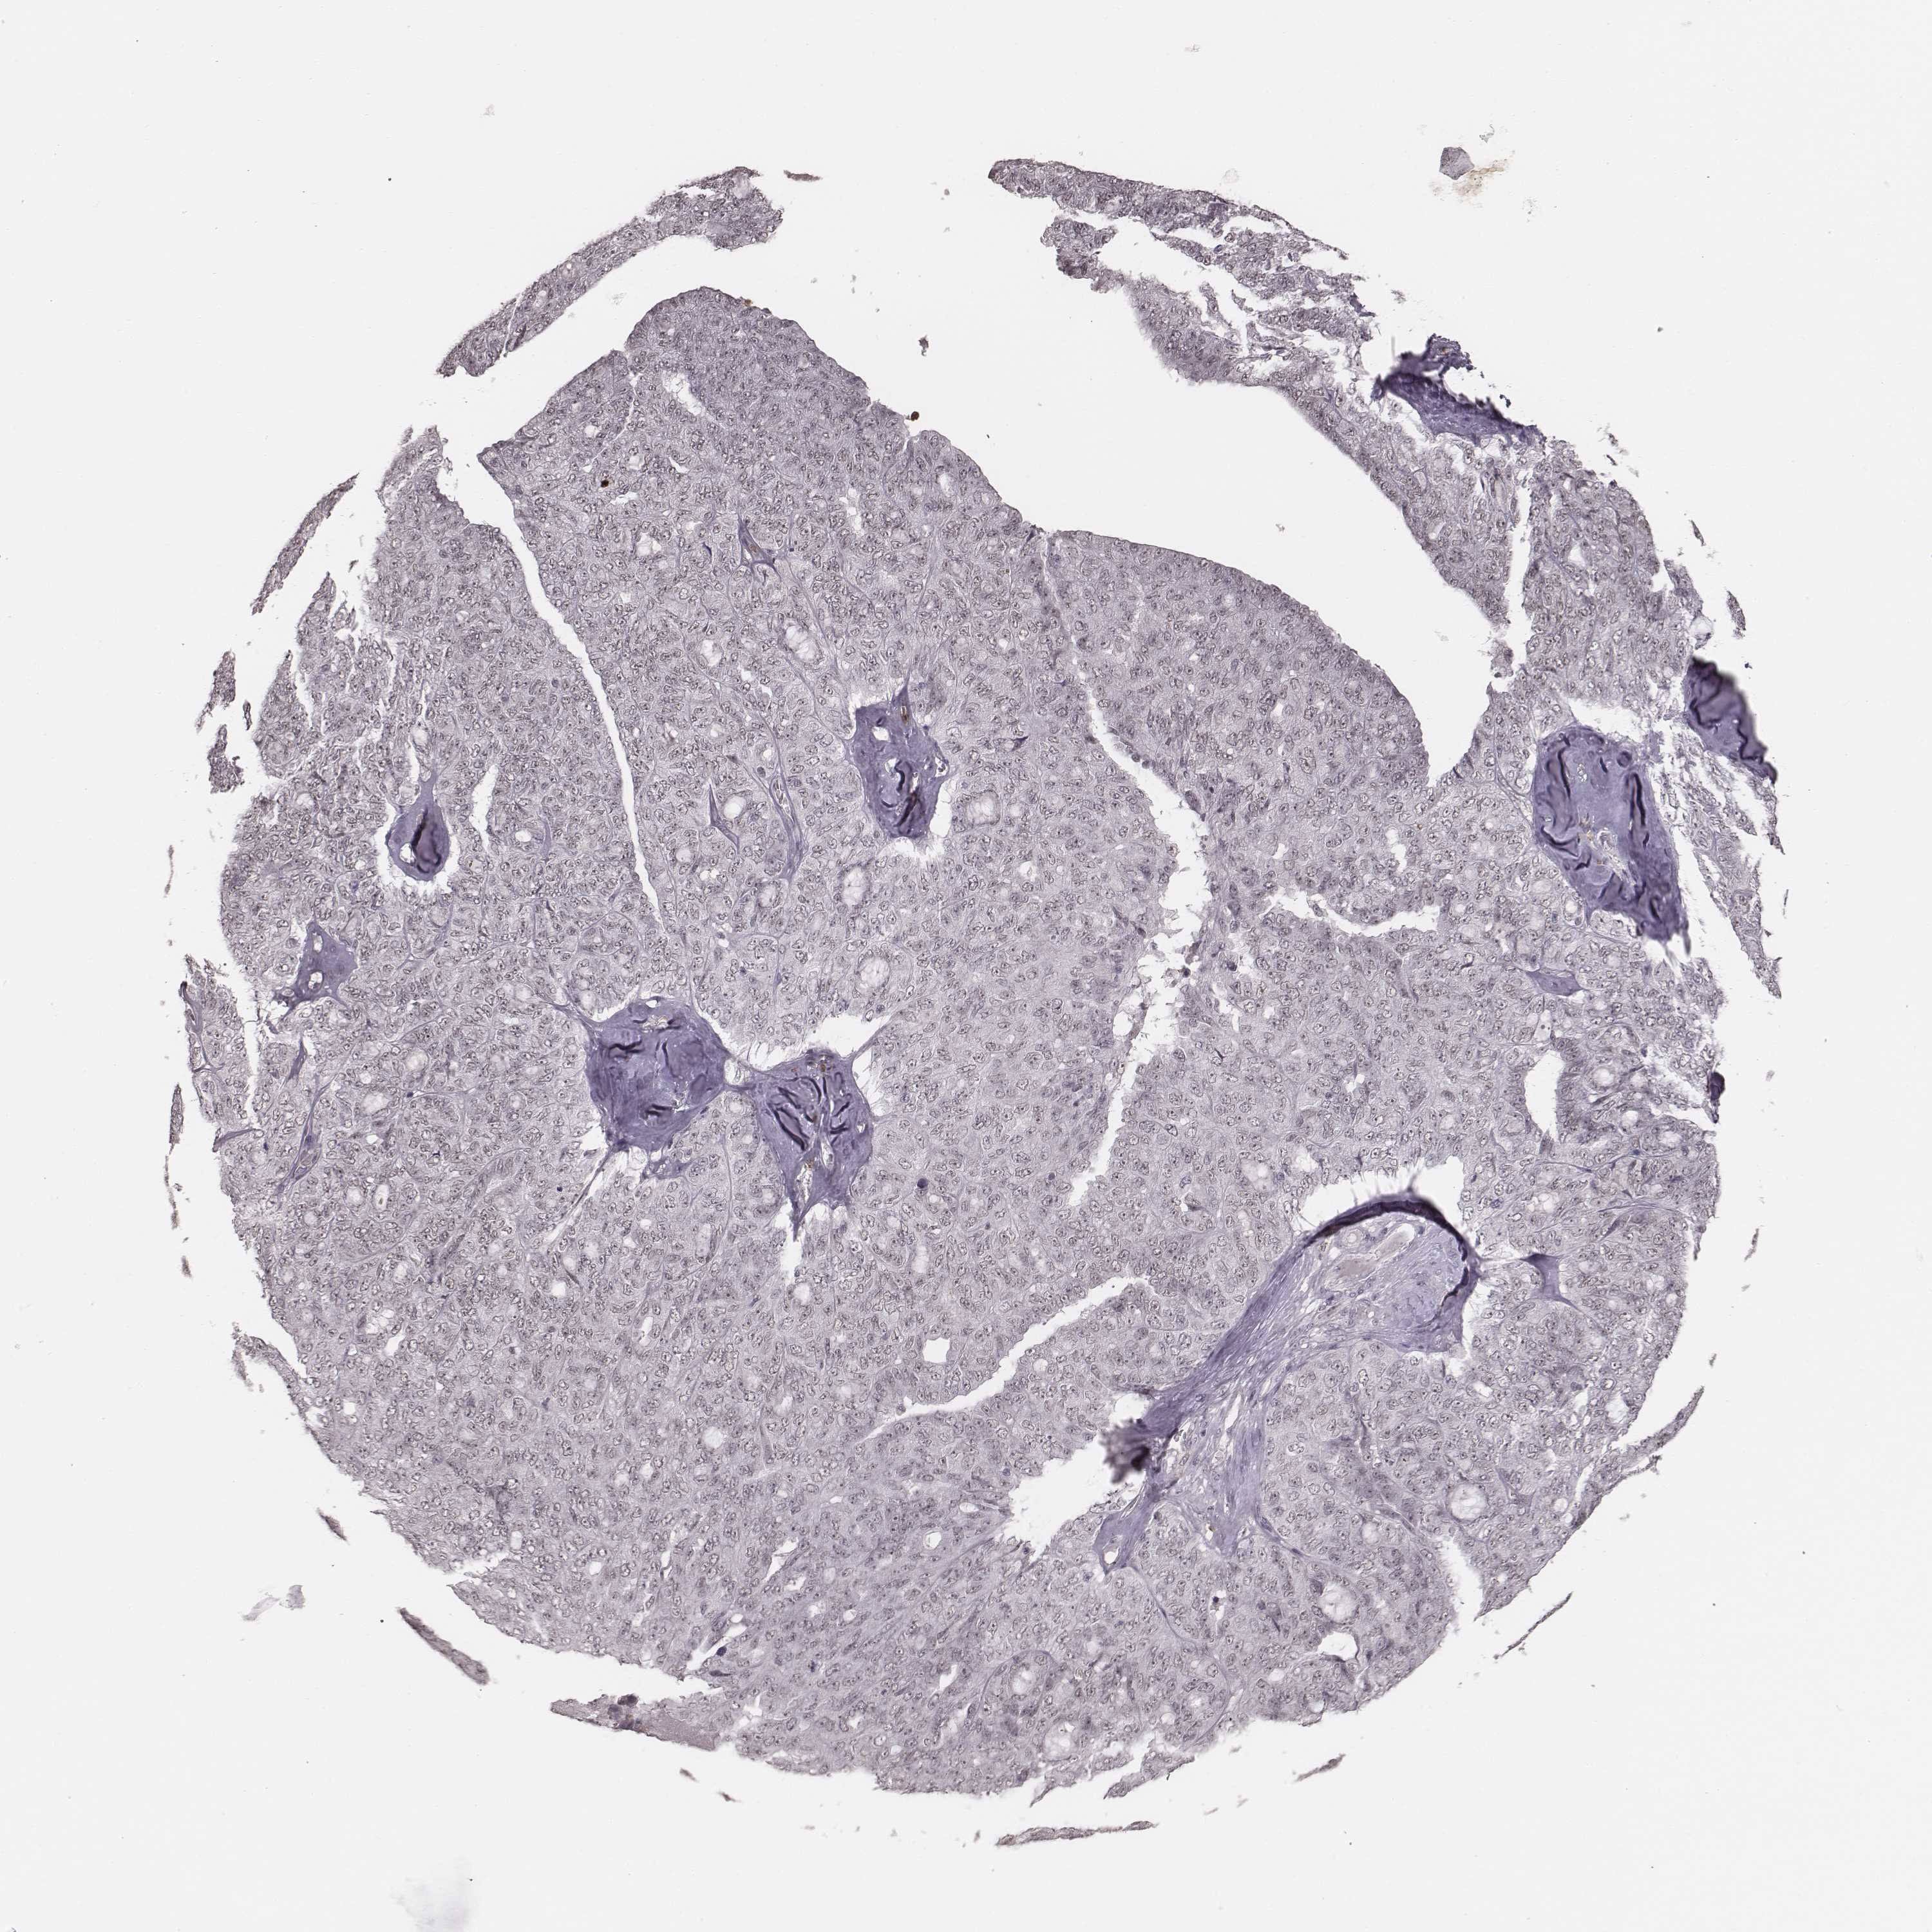

OVARIAN CANCER - Protein expressioni

A mouse-over function shows sample information and annotation data. Click on an image to view it in a full screen mode. Samples can be filtered based on level of antibody staining by selecting one or several of the following categories: high, medium, low and not detected. The assay and annotation is described here.

Note that samples used for immunohistochemistry by the Human Protein Atlas do not correspond to samples in the TCGA dataset.

Antibody stainingi

Antibody staining in the annotated cell types in the current human tissue is reported as not detected, low, medium, or high, based on conventional immunohistochemistry profiling in selected tissues. This score is based on the combination of the staining intensity and fraction of stained cells.

Each image is clickable and will lead to virtual microscopy that enables deeper exploration of all samples and also displays staining intensity scores, fraction scores and subcellular localization as well as patient and tissue information for each sample.

Antibody HPA070395

Staining

High

Medium

Low

Not detected

Intensity

Strong

Moderate

Weak

Negative

Quantity

>75%

75%-25%

<25%

None

Location

Nuclear

Cytoplasmic/membranous

Cytoplasmic/membranous,nuclear

Cystadenocarcinoma, serous, NOS

Cystadenocarcinoma, mucinous, NOS

Carcinoma, endometroid